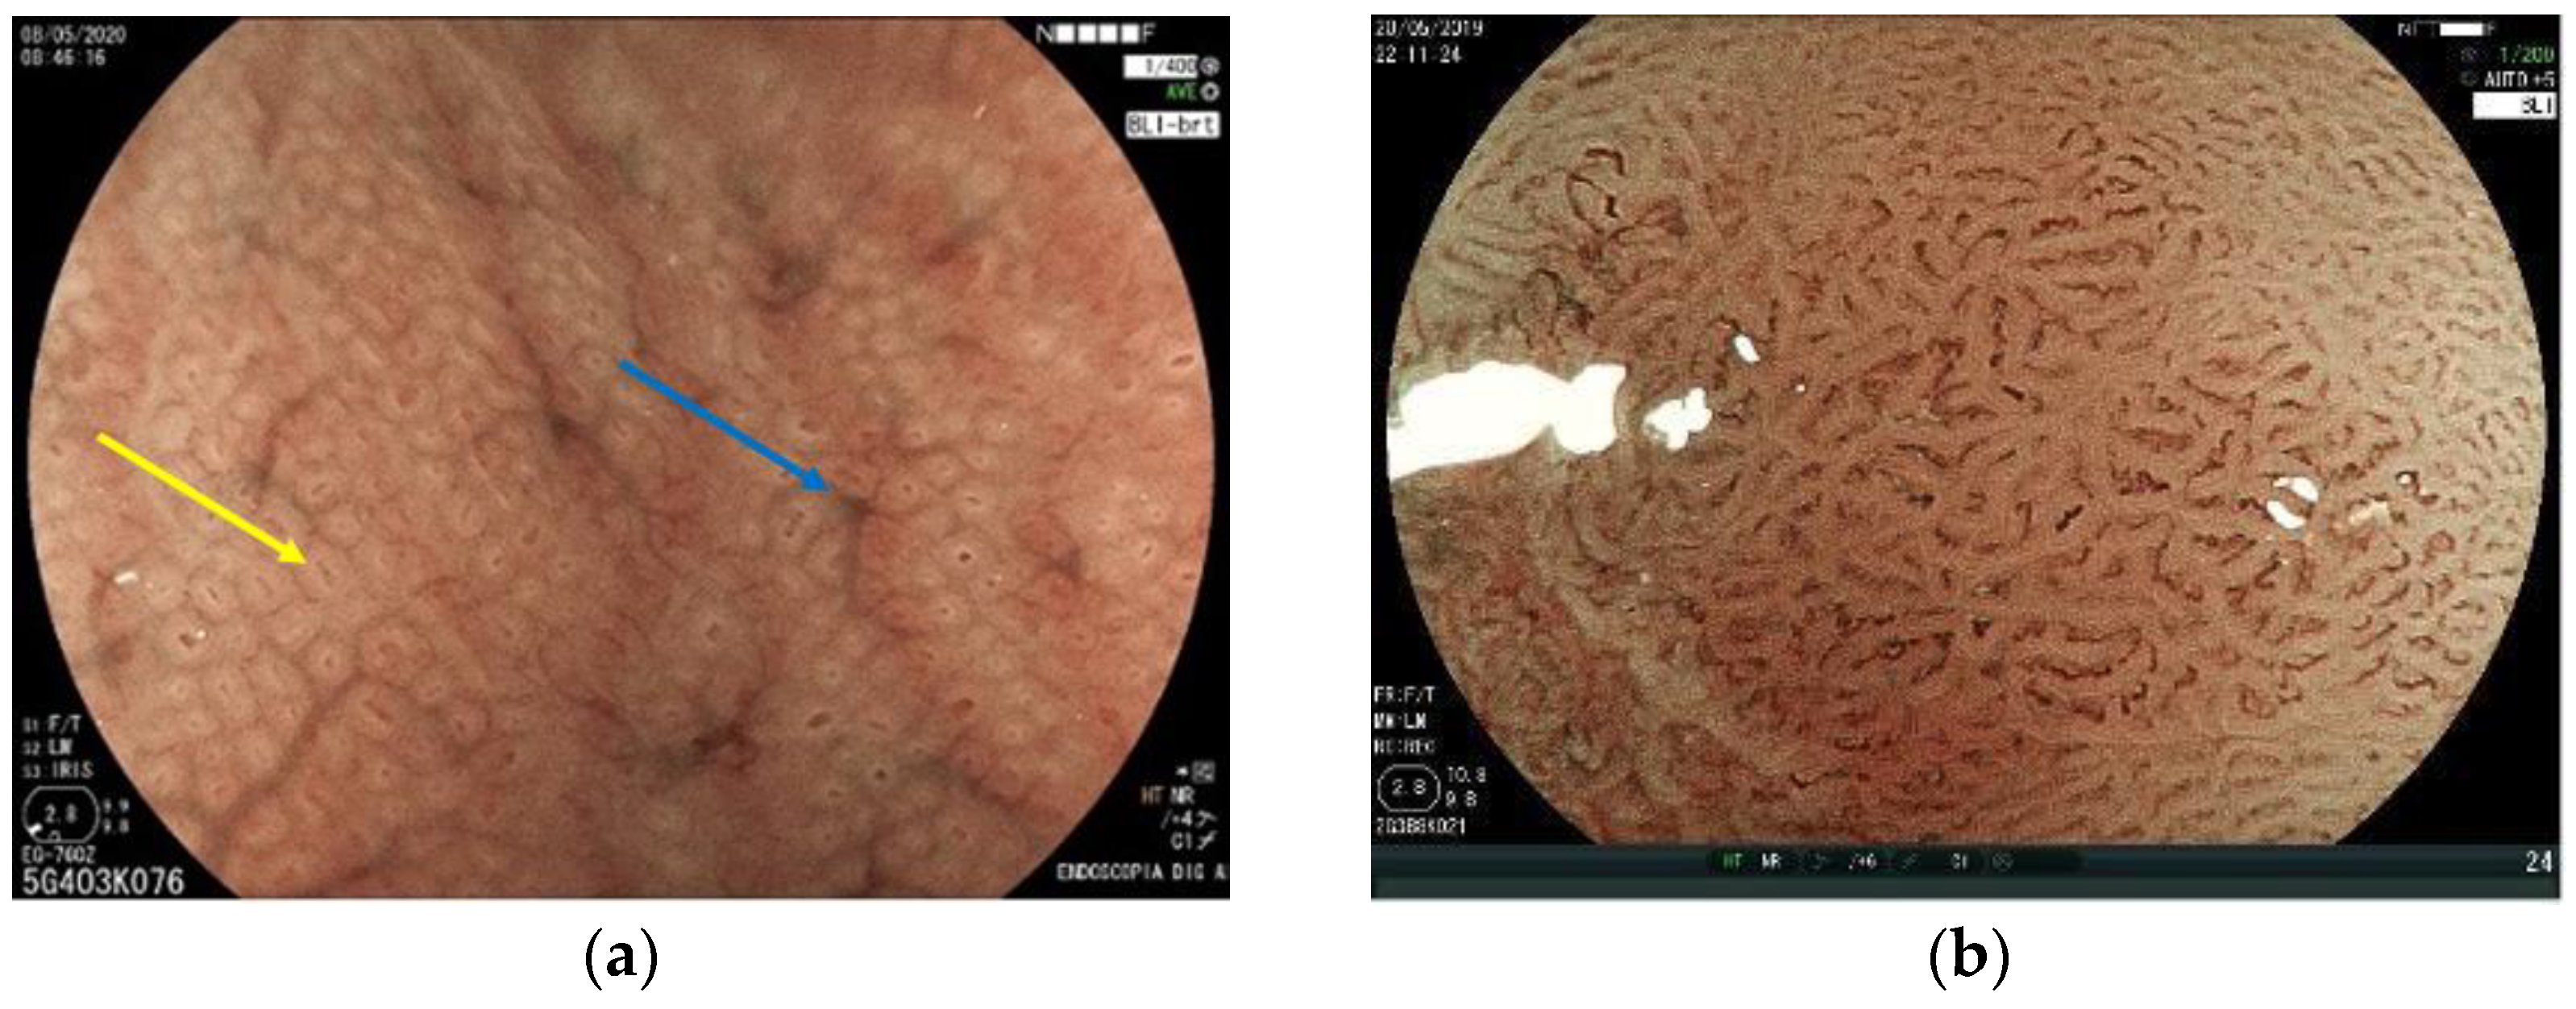

5. Virtual Chromoendoscopy

6. Magnifying Endoscopy